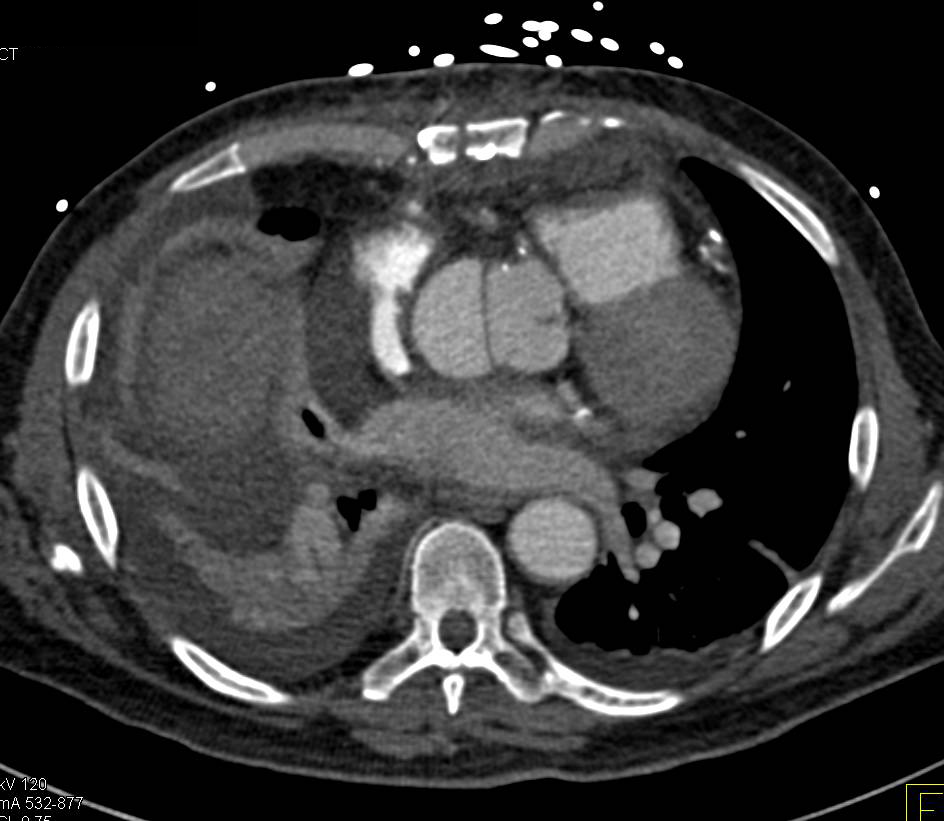

CCTA: Left Anterior Descending Coronary Artery (LAD) Stenosis Approaches 50% with Noncalcified Plaque